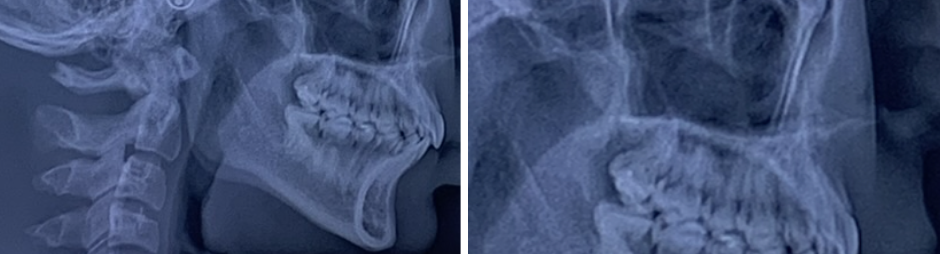

See images:

The pre mentioned “void” is visible on x-ray imaging

See images:

The pre mentioned “void” is visible on x-ray imaging